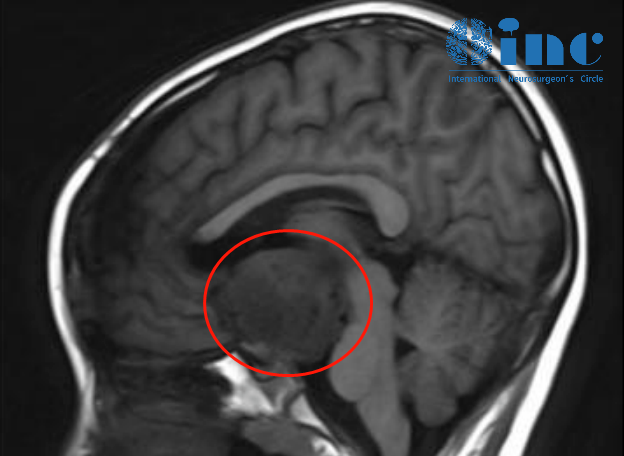

躺在床上的这名可爱患儿年仅9岁,4个月前开始出现头痛,头部核磁检查,考虑颅咽管瘤。已经在国内经历过一次开颅手术的悦悦并没有因此摆脱脑瘤。医生表示手术时发现是视神经胶质瘤,一旦切除,孩子就会失去视力。但随着肿瘤的生长,孩子仍可能视力不保。而且一开始手术的病理报告提示竟是鞍区低级别胶质瘤,考虑毛细胞星型细胞瘤WHO 1级,不是术前诊断的颅咽管瘤。毛细胞星型细胞瘤只要达到顺利切除,孩子可以长期生存。

悦悦父母又带着他辗转多家医院,然而也都是表示手术风险很大,建议先化疗。但是对于治疗已经有认识的他们觉得如果有手术机会,还是希望孩子可以一次顺利切除肿瘤,保住视力。“只要巴教授说可以做手术,我们就不做化疗了”,悦悦父母在找到巴教授之后重拾信心。在视频连线询问情况、观看影像资料后,巴教授对患儿病情进行了详细评估。“这个小男孩有明确的手术指征。根据我的经验,这个肿瘤可以顺利地切除。我可以在苏州为这个孩子手术。”